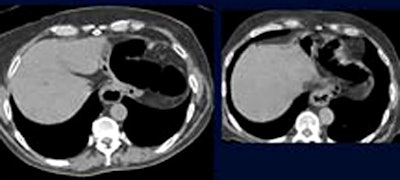

![]() |

| Hiatal hernias constituted 28% of moderately important findings. |